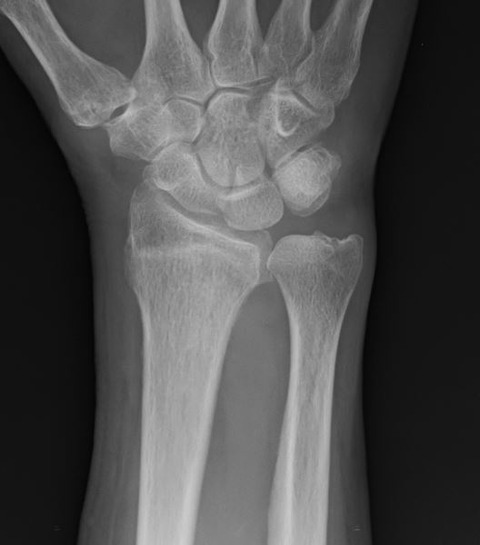

しかし、単純X線像をみると、何となく普通ではありません。??? と思って、側面像を見ると、橈骨遠位端背側の皮質骨が変な感じです。

これって、骨折ではないのか? ご本人に何度も念押ししましたが、やはり転倒等のエピソードはないとのことです。受け答えはしっかりしており、認知症でもなそうです。

念のためにMRIを撮像すると、やはり橈骨遠位端骨折のようです。圧痛点も関節ではなく、橈骨遠位端なので、画像と身体所見が一致しました。